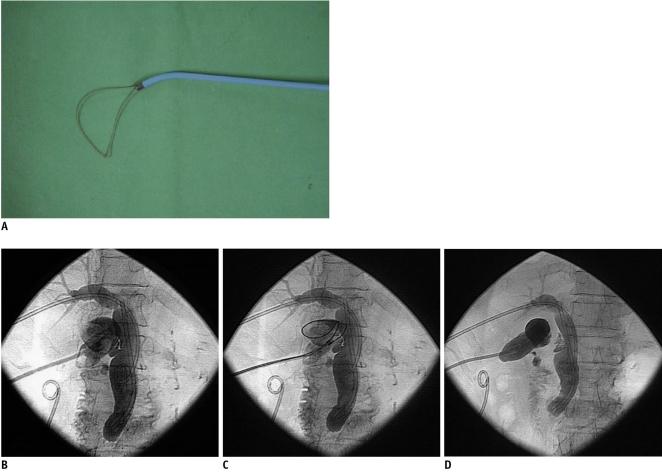

Sixty-three consecutive patients of high surgical risk with acute calculous cholecystitis underwent percutaneous transhepatic gallstone removal under conscious sedation. The stones were extracted through the 12-Fr sheath using a Wittich nitinol stone basket under fluoroscopic guidance on three days after performing a percutaneous cholecystostomy. Large or hard stones were fragmented using either the snare guide wire technique or the metallic cannula technique.

Gallstones were successfully removed from 59 of the 63 patients (94%). Reasons for stone removal failure included the inability to grasp a large stone in two patients, and the loss of tract during the procedure in two patients with a contracted gallbladder. The mean hospitalization duration was 7.3 days for acute cholecystitis patients and 9.4 days for gallbladder empyema patients. Bile peritonitis requiring percutaneous drainage developed in two patients. No symptomatic recurrence occurred during follow-up (mean, 608.3 days).